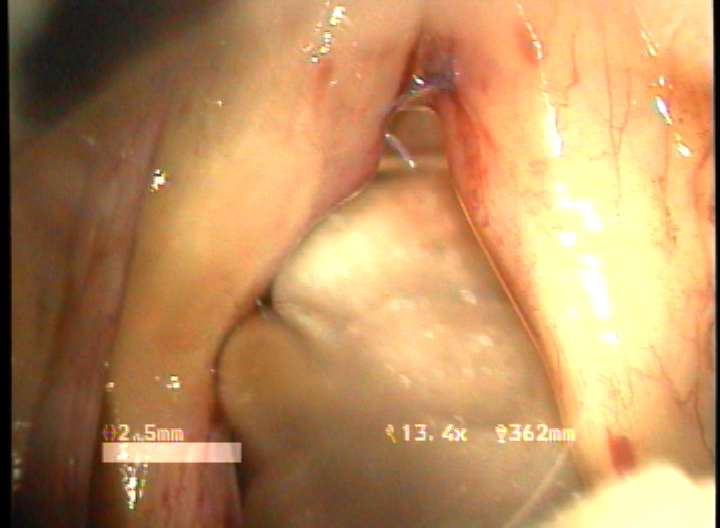

double rotational microflap laryngoplasty 수술 동영상... more >

결과 : 음성개선에 대한 주관적인 평가로서 수술전 Voice Handicap Index는 평균 19.7 에서 술후 11.5로 감소하였다. 공기역학적인검사상 성문하압은 5.5에서 4.5로 감소되었으며, 최대발성시간 13.7에서 16.1로 증가되었다. 음성분석검사상 sPPQ, sAPQ, NHR, SPI, DSH가 모두 통계학적으로 유의하게 감소하였다. 후두스토로보스코피검사상 모든 례에서 재발의 징후없이 성대점막파동의 의미있는 호전이 나타났다. 합병증으로 1례에서 염증성 육아종형성이 관찰되었으나 미세피판의 괴사나 탈락은 관찰되지 않았다.

결론 : 전성문횡격막의 새로운 수술방법으로서 double rotational microflap laryngoplasty는 일차수술로 만족스러운 음성학적 치료결과를 얻을 수 있는 매우 유용한 술식이라 사료된다.